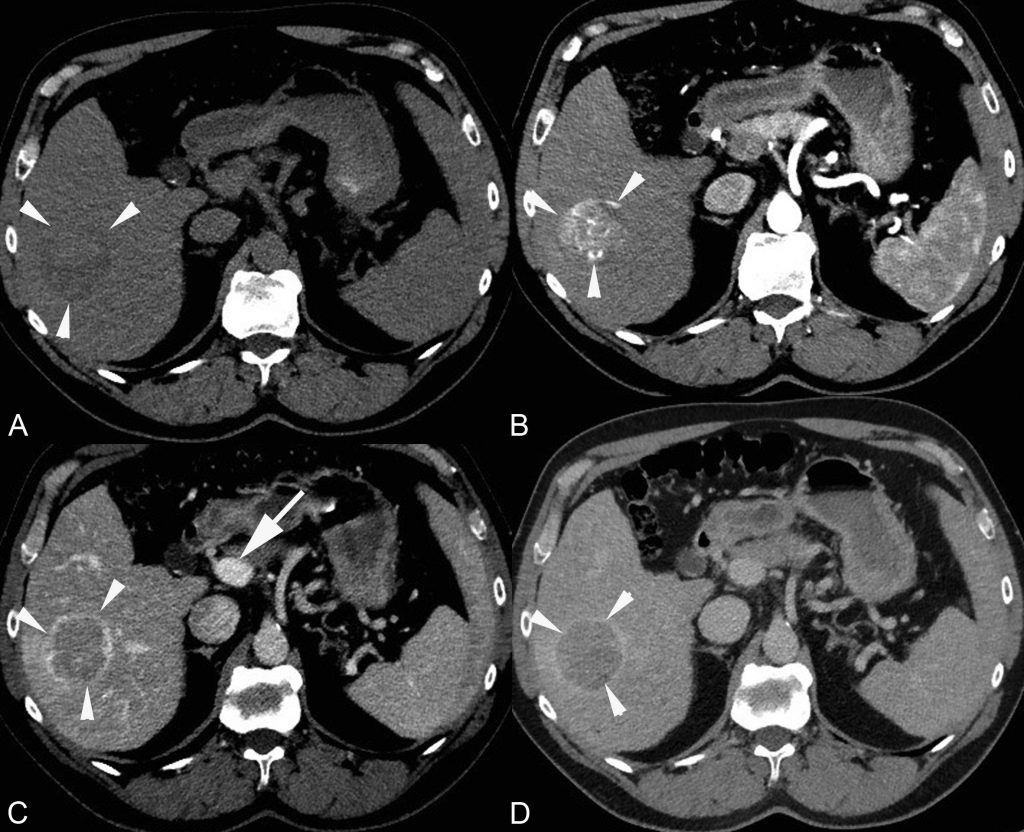

Au scanner, elle est spontanément légèrement hypodense par rapport au foie avec parfois des remaniements hémorragiques (hyper- ou isodenses par rapport au foie) (figure 16.2).

Fig. 16.2. Exemple d’examen scanner d’un CHC typique chez un patient atteint de cirrhose virale C.

(A) Coupe sans injection : tumeur (têtes de flèches) du foie droit avec aspect hétérogène, discrètement hypodense par rapport au foie adjacent. (B) Temps artériel : prise de contraste hétérogène de la lésion alors que le parenchyme hépatique ne se rehausse quasi pas. (C) Temps portal : rehaussement du foie par le flux porte (flèche). Le CHC est isodense au foie avec un rehaussement périphérique (capsule). (D) Temps tardif : rehaussement diffus du parenchyme hépatique et lavage de la lésion.

Source : CERF, CNEBMN, 2022.

Après injection de produit de contraste au scanner ou en IRM, le CHC est caractérisé par un rehaussement important au temps artériel suivi d’un lavage au temps veineux portal ou tardif (figures 16.2 et 16.3), c’est-à-dire que la lésion devient plus hypodense ou hypo-intense que le foie adjacent.